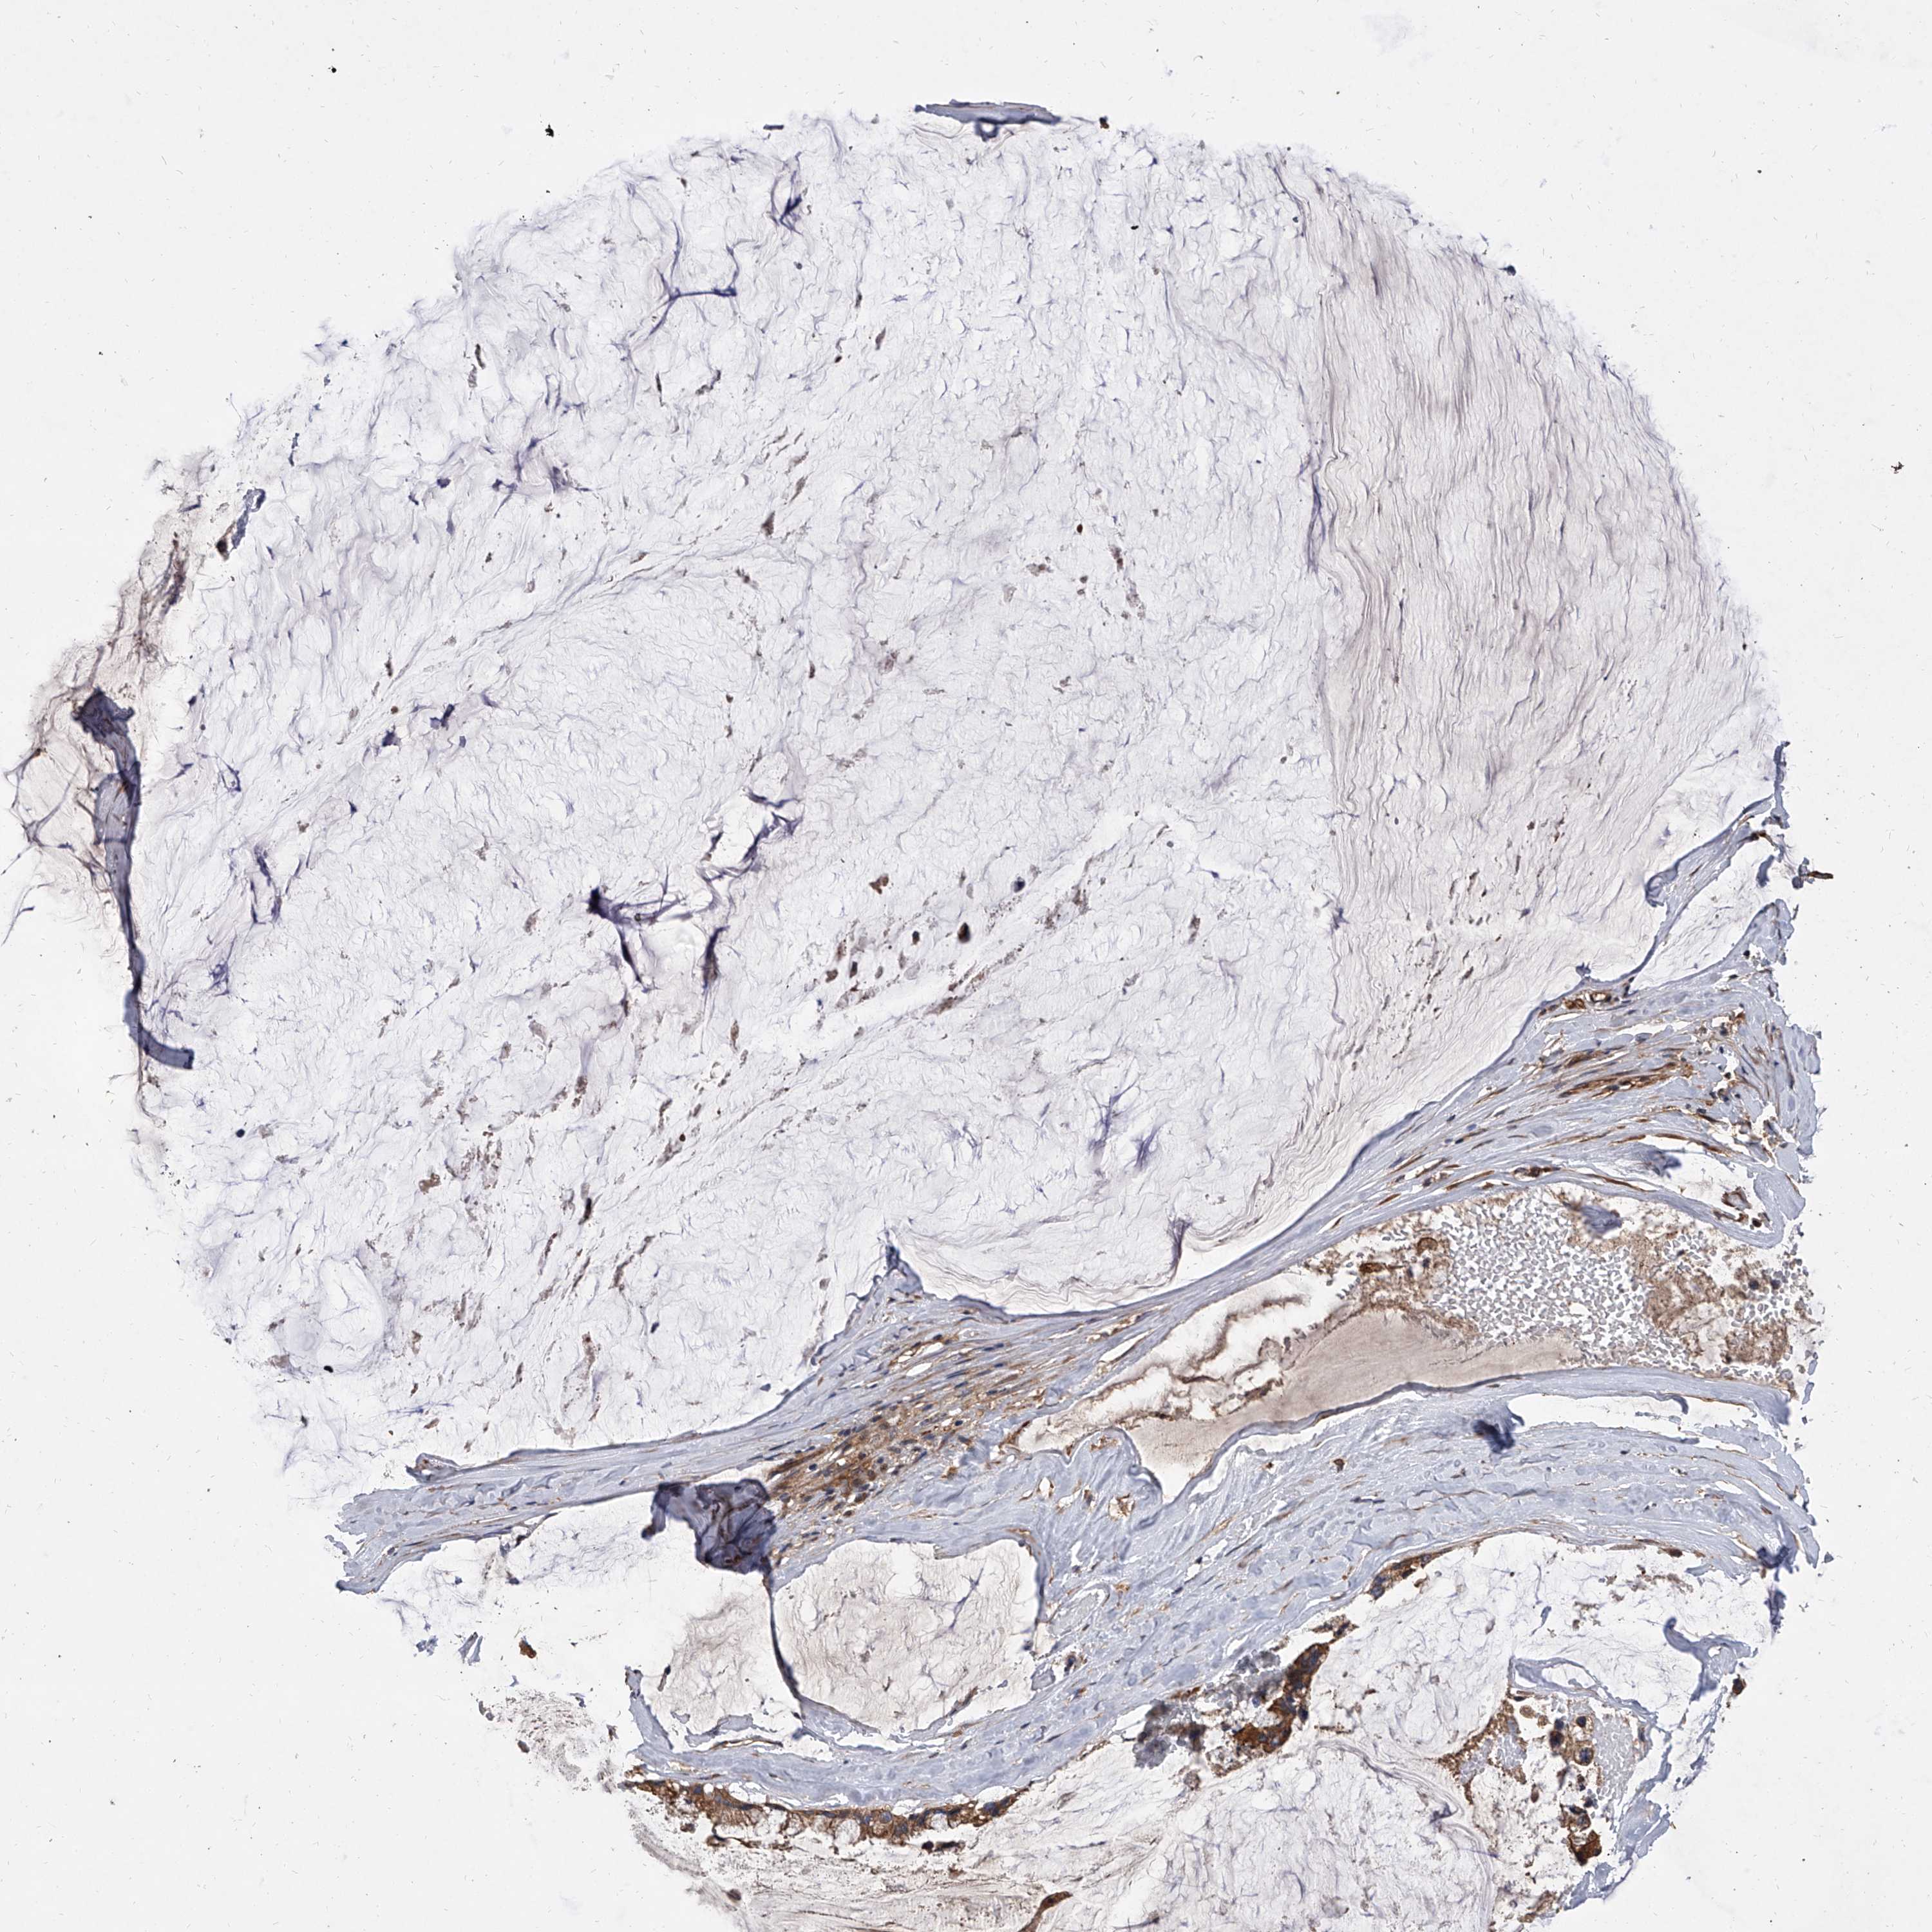

OVARIAN CANCER - Protein expressioni

A mouse-over function shows sample information and annotation data. Click on an image to view it in a full screen mode. Samples can be filtered based on level of antibody staining by selecting one or several of the following categories: high, medium, low and not detected. The assay and annotation is described here.

Note that samples used for immunohistochemistry by the Human Protein Atlas do not correspond to samples in the TCGA dataset.

Antibody stainingi

Antibody staining in the annotated cell types in the current human tissue is reported as not detected, low, medium, or high, based on conventional immunohistochemistry profiling in selected tissues. This score is based on the combination of the staining intensity and fraction of stained cells.

Each image is clickable and will lead to virtual microscopy that enables deeper exploration of all samples and also displays staining intensity scores, fraction scores and subcellular localization as well as patient and tissue information for each sample.

Antibody HPA031443

Staining

High

Medium

Low

Not detected

Intensity

Strong

Moderate

Weak

Negative

Quantity

>75%

75%-25%

<25%

None

Location

Nuclear

Cytoplasmic/membranous

Cytoplasmic/membranous,nuclear

Cystadenocarcinoma, serous, NOS

Carcinoma, endometroid

Cystadenocarcinoma, mucinous, NOS

Carcinoma, NOS